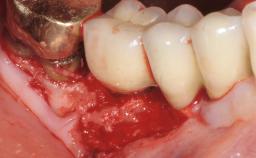

Late Presentation of Peri-Implant Mucositis Requiring Soft-Tissue Augmentation and Esthetic Crown Lengthening at Implant Site 11

Biological or technical complications around implant-supported prostheses place a significant burden on patients as well as the surgical and restorative team. Inflammation of the peri-implant soft tissues is often the first sign that something has gone awry. While there is never a good time for a complication, late presentation of inflammation in the soft tissues around a long-standing prosthesis triggers a period of research and review of the case in order to ascertain the treatment history and its possible contribution to the etiology of the situation. This becomes more complicated in situations where a patient has not received regular maintenance and clinical/radiographical examinations due to personal, financial, or professional reasons. When the complication occurs in the esthetic zone, the complexity of the situation expands exponentially, as the only acceptable outcome in the patient’s eyes will be the maintenance of the esthetics of the prosthesis.